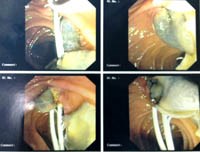

Nội soi mật tụy ngược dòng (ERCP) được xem là kỹ thuật chuẩn vàng trong chẩn đoán hình ảnh ở đường mật trên các bệnh nhân nhiễm trùng mạn tính. Nó cũng hỗ trợ trong quản lý ca bệnh sán lá gan lớn, cần phải cắt cơ vòng dưới hướng dẫn của ERCP và loại bỏ sán trưởng thành kẹt do nhiễm trùng mạn tính và gây tắc đường mật.